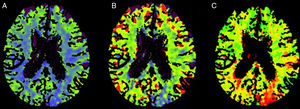

Two patients showed normal perfusion, with no asymmetries in CBV, CBF, or time to peak (Tmax). The most frequent finding in the rest of the sample was longer time to peak (Tmax), with varying CBF and CBV (Figs. 1–3).

Perfusion CT scan from patient 6. Right hemisphere syndrome (NIHSS score: 12). (A) Increased CBF in the right hemisphere. (B) Increased CBV in the right hemisphere. (C) Shorter Tmax at a similar location in the cortex. Changes do not clearly correspond to a specific vascular territory. CT-angiography revealed no large-vessel occlusion.